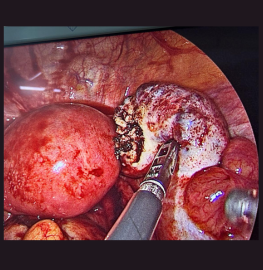

27yr female with acute pain abdomen for 2days. Admitted. Pregnancy test positive USG showed mild to moderate fluid in abdomen. Haemoglobin was decreasing. Decided to do diagnostic laparoscopy. After entering into the a dome there was approx 1 lit blood inside. Continuous bleeding from right ovarian cyst. Cauterisation and biopsy done.